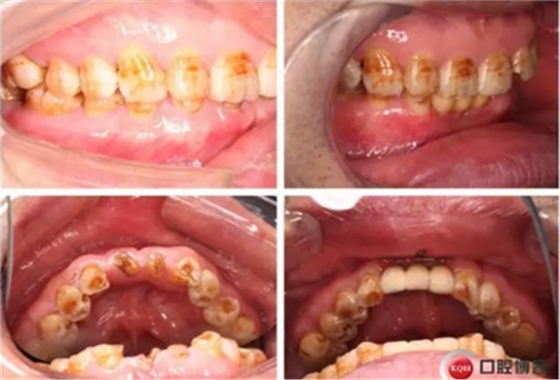

治療前后照片顯示患者上下臨床牙冠比例協(xié)調(diào),患者對(duì)臨時(shí)修復(fù)體效果十分滿意。當(dāng)然有待后期愈合及長(zhǎng)期的臨床隨訪,以觀察遠(yuǎn)期臨床效果。將水激光應(yīng)用臨床冠延長(zhǎng),有利于精準(zhǔn)去除骨量,利于術(shù)后愈合。而MINI型一段式種植體滿足骨寬度不足,及臨時(shí)修復(fù)打下堅(jiān)實(shí)基礎(chǔ)。

下圖是術(shù)后照片 治療過程 術(shù)前測(cè)量上下牙長(zhǎng)度比例,確定水激光冠延長(zhǎng)深度約3mm,拔除31、41,在術(shù)區(qū)減低牙槽嵴高度,32、42位點(diǎn)種植MINI型一段式種植體,使用臨時(shí)愈合帽行暫時(shí)性修復(fù)。